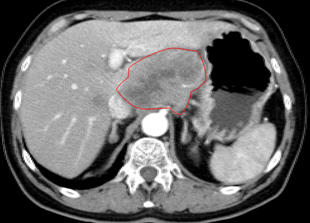

郭林治疗前CT显示肿块,活检证明为胰腺癌

半年后复查CT显示胰腺肿瘤缩小,PET上无活性,提示肿瘤坏死。肝转移灶消失(此图未显示)